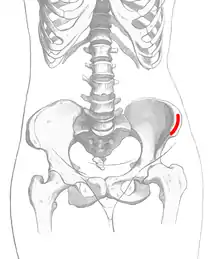

After creation of the pocket, but before suturing closed the gingiva a bone graft is placed into the bony defect. This is most commonly harvested from the anterior hip but can also be obtained from other sites, donor bone, or bioactive materials such as bone morphogenic proteins. Once packed the cleft is filled with bone material the gingiva is sutured closed to create a water tight closure between the mouth and the nose. [4]

Source of bone graft

The most common source of the bone graft is from the iliac crest,[6] harvested at the time of the cleft closure. Other sources such as the chin, and posterior iliac crest, or skull can also be used. Artificial grafts such as demineralized bone, recombinent bone morphogenic protein or a mix of harvested bone and artificial grafts have also been used. Insufficient data exists to show that one is beneficial over the other.[1]